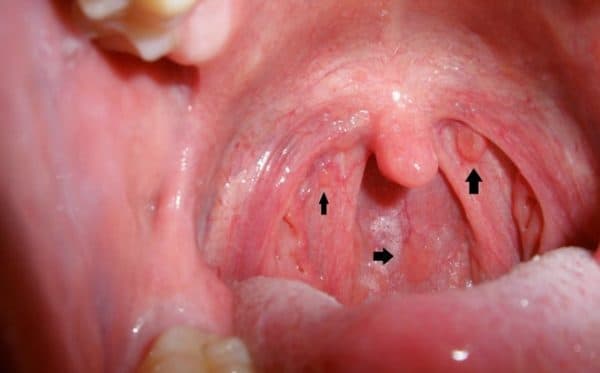

Bệnh tai mũi họng ở người lớn là một trong những nguyên nhân hàng đầu gây ra nhiều bệnh lý viêm đường hô hấp mạn tính và có thể gây ra biến chứng nguy hiểm là ung thư vòm họng. (ảnh minh họa)

Sau đó, tôi nghe người nhà giới thiệu bệnh viện Thu Cúc và tôi quyết định đến Thu Cúc để khám tai mũi họng. Bác sĩ nội soi tai mũi họng cho tôi xong và phát hiện thấy một số biểu hiện bất thường như u sùi loét ở vòm mũi họng. Bác sĩ đã chỉ định cho tôi làm tầm soát ung thư ngay và phát hiện ra tôi bị ung thư vòm họng. Thực sự ngỡ ngàng, tôi chỉ nghĩ mình bị mắc bệnh tai mũi họng thông thường thôi, nào ngờ bệnh lại nặng đến vậy. Từ đó đến nay tôi bắt đầu quá trình điều trị ung thư tại bệnh viện Thu Cúc.